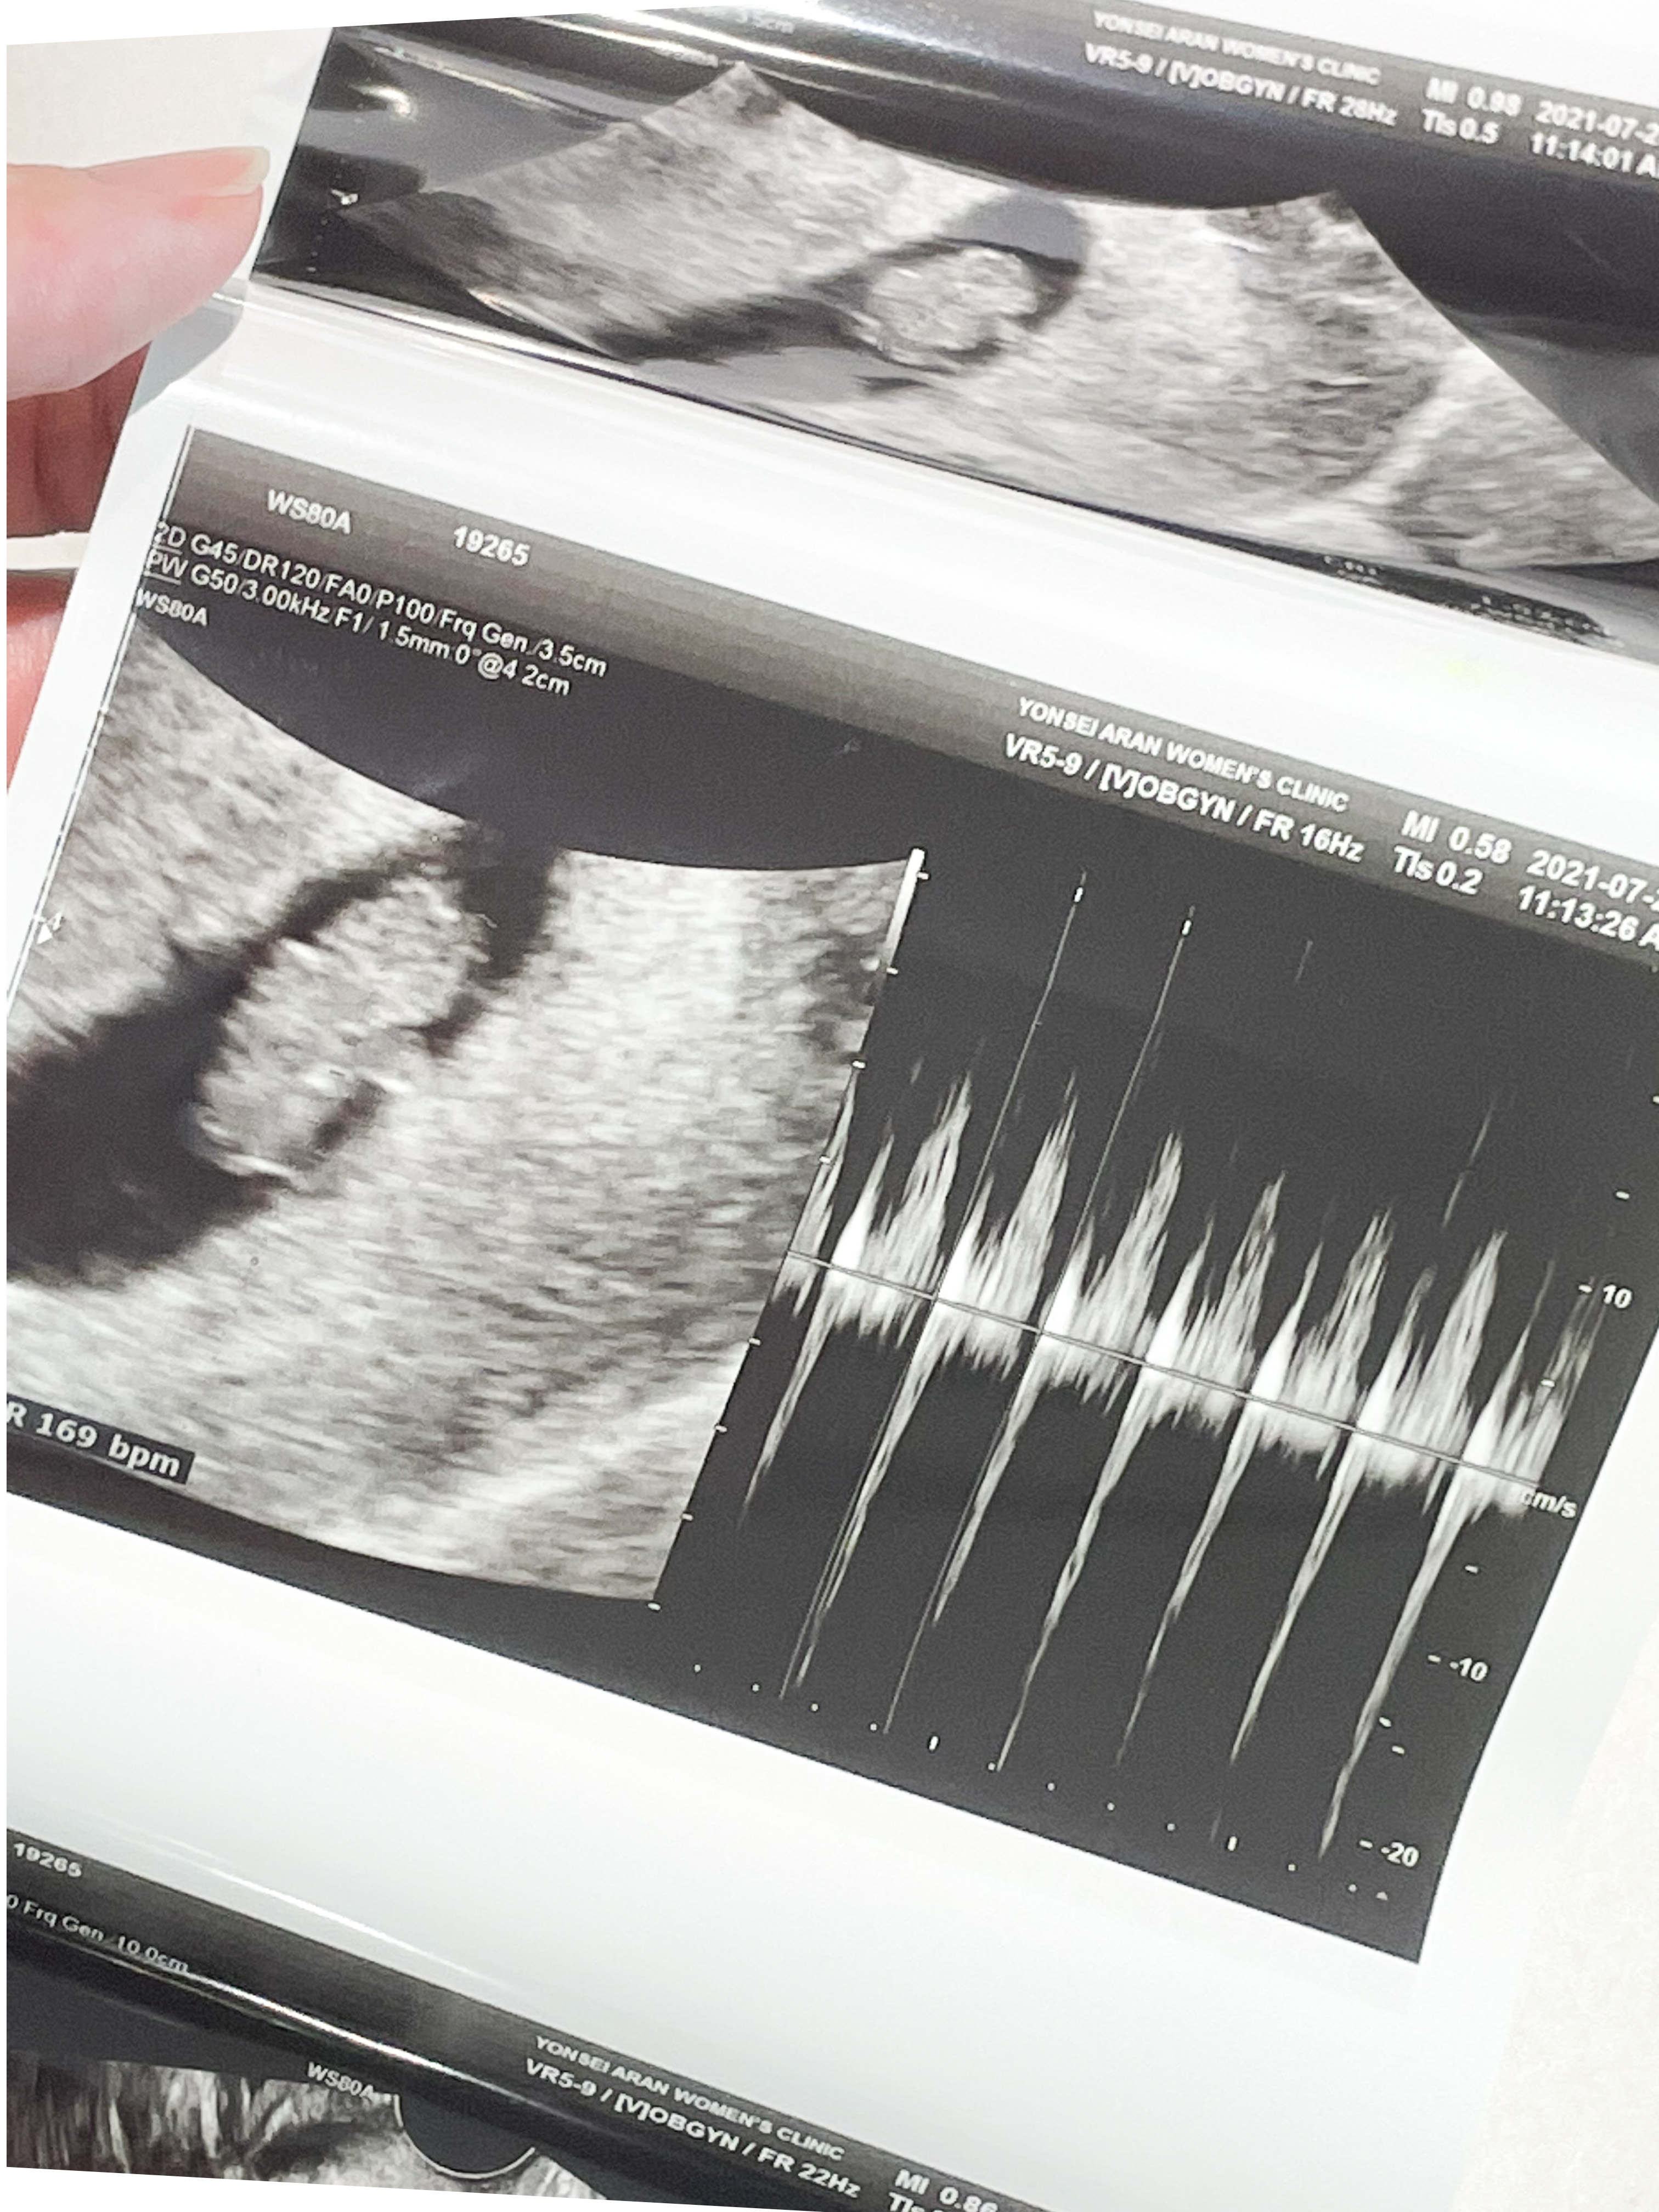

8주 1일

입덧약 처방 받으러 간 김에 초음파도 한 번 봤다.

막대기 같이 생겼던 아기가 어느덧 통통해졌고 팔다리까지 있었다.

쌤이 젤리곰이라고 너무 귀엽다고 하셨는데,

내 눈에는 물개 같았다.

심장도 잘 뛰고 있었다.

뇌 쪽이 구멍이 뚫려 있었는데 정상이라고 하셨다.